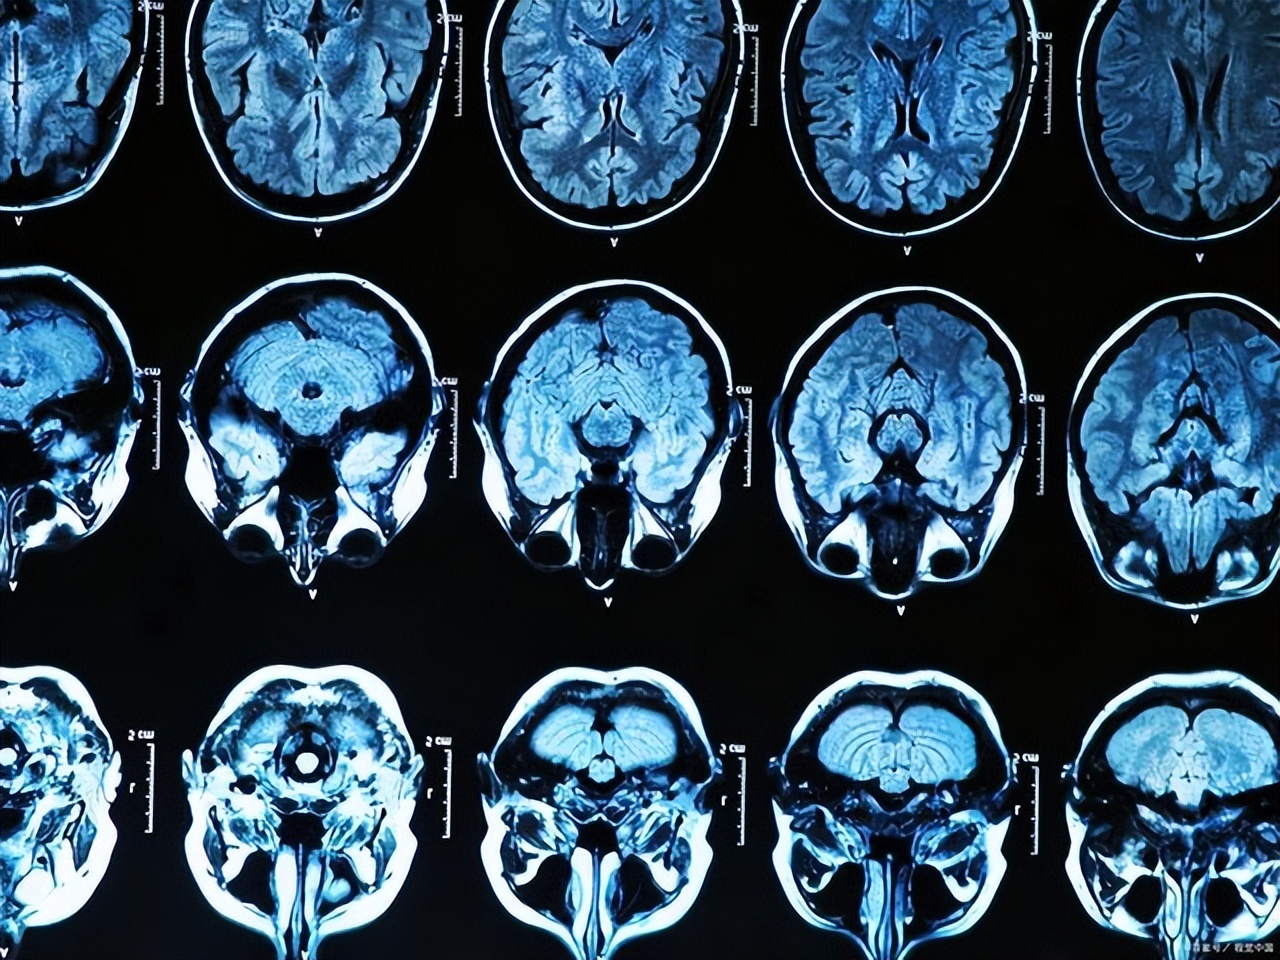

磁共振机器是诊断心脑血管、肿瘤和神经等重症疾病的影像长枪,能很好地给临床诊断带来更准确的结果。

核磁共振或者磁共振成像(MRI),是一种被广泛应用于医疗和临床的检测手段,是通过无线电波、磁场和人体内的原子核作用。

利用检测完器官后,就可以获取器官内部的高清晰的影像,因此就能准确地发现人体中各个器官潜藏的病变风险,及时干预,堪称病灶的“滤网”。

和其他技术相比,磁共振技术不需要借助任何具有放射性的物质的帮助,这也让核磁共振成为了一种无创、安心、同时兼具非入侵性的医诊方式。

在医学领域内,其主要被应用在影像分析和研究,如人体内的毒瘤、心脏病、中风等都可以被它提前检测到,如此一来能省去后续不少的费用花销。